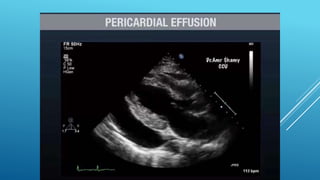

Phases of Hemodynamic changes in Tamponade,

With Accumulation of pericardial fluid

Impairs Relaxation and Filling of Ventricles,

Requiring Higher Filling Pressure;

during this phase,

LV & RV Filling Pressures are

Higher than IntraPericardial Pressure

Phase II

With further Fluid Accumulation,

Pericardial Pressure increases

Above Ventricular Filling Pressure,

Resulting in Reduced Cardiac Output

Phase III

With further Decrease in Cardiac Output ,

which is due to Equilibration of :;:

Pericardial and (LV) Filling pressures